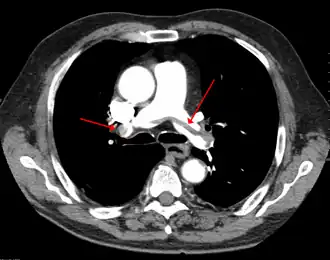

Tomografia computadorizada de tórax com agente de radiocontraste mostrando múltiplos defeitos de enchimento dos principais ramos das artérias pulmonares, devido a embolismo pulmonar crônico e agudo.